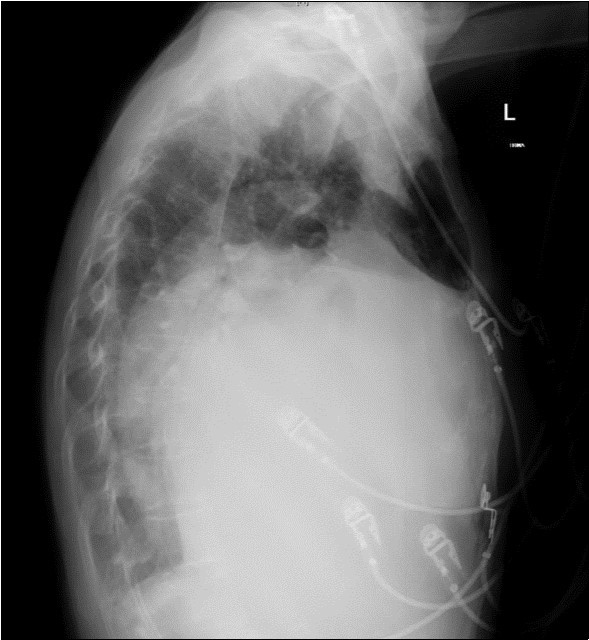

A 64-year-old woman was admitted to the Intensive Care Unit (ICU) after a medical emergency team (MET) call from the cardiology ward due to a reduced level of consciousness and respiratory distress. Past medical history included rheumatic fever as a child and chronic atrial fibrillation. She had been admitted to hospital 3 days previously with worsening shortness of breath. On observation she was drowsy but rousable to voice, with a respiratory rate of thirty breaths per minute. Examination revealed a raised jugular venous pressure, a pan-systolic murmur as well as a long mid-diastolic murmur, both loudest at the apex and radiating to the axilla, a soft first heart sound, a displaced tapping apex beat, and bi-basal medium-intensity inspiratory crepitations. Her electrocardiogram showed atrial fibrillation with a rapid ventricular response of 126 beats per minute. Her arterial blood gas demonstrated an acute on chronic respiratory acidosis with a pH 7.02, PaCO2 176 mmHg, and a HCO3- of 43 mmol/L. An antero-posterior (AP) chest x-ray on admission displayed cardiomegaly, splayed carina and hilar venous congestion, with a lateral film showing the left atrium occupying a significant part of the chest cavity (see Figure 1a, Figure 1b).

Figure 1b.Chest X-ray Lateral view. Findings showing enlarged left atrium occupying large amounts of the thoracic cavity, both horizontally and vertically